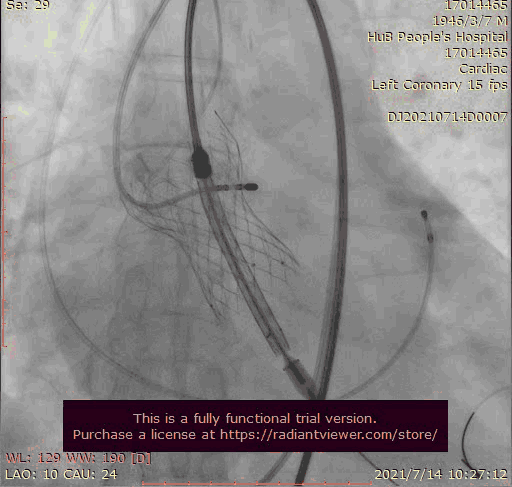

奇思妙想使用射频消融大头压住支架至窦底

在大头压迫支架下释放第二个瓣膜

第二个支架完美释放固定第一个支架

1.在第一次释放瓣膜时,由于患者主动脉根部瓣上瓣下均比瓣环平面大,受到血流的冲击,瓣膜滑至较深的位置,使用venus-A PLUS回收

2.回收后重新定位释放,由于第一次滑至较深,第二次稍微卸力后瓣膜跳至窦上,使用venus-A PLUS回收,再次重新定位

3.第三次释放瓣膜后位置的把控非常精准,瓣膜位置合适,但由于稳定性差,撤出输送系统时瓣膜跳至窦上,此时非常凶险,瓣膜无法固定住,受到血流的冲击,可能对升主造成夹层的风险,一般会选择开胸取出,但风险非常,在江洪教授的思考下和团队的讨论下,决定使用射频消融大头穿过支架网孔使瓣膜到窦底固定,在此基础上释放第二个瓣膜,使用第二个瓣膜花冠固定住第一个瓣膜

4.第四次瓣膜释放后两个瓣膜均稳定住,造影超声评估无瓣周漏,二尖瓣反流也基本消失,观察一小时后,无其他情况。患者顺利下台